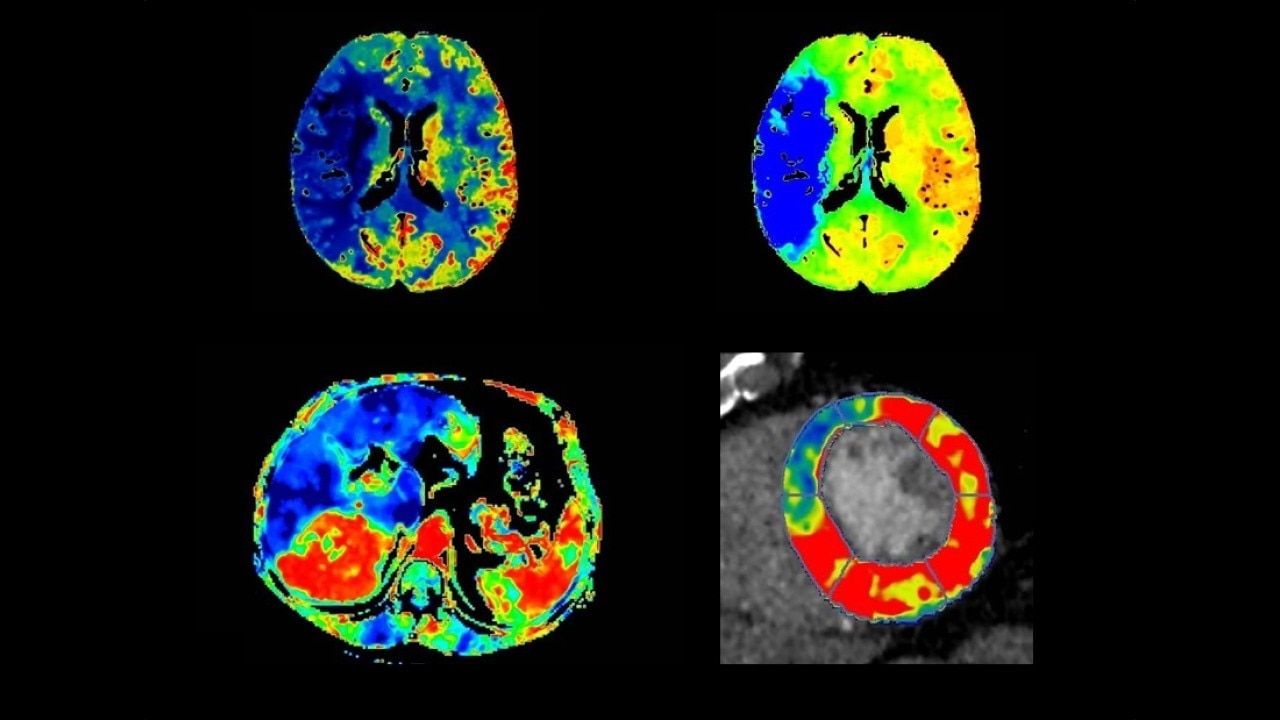

Brain perfusion

Easy-to-use automated workflow for CT stroke and tumor angiogenesis evaluation

Brain stroke protocol

• Image Registration to minimize the effects of patient movement

• Bone Removal to remove the cranium automatically from the dataset

• Deep Learning brain ventricle segmentation to prevent ventricular matter inclusion in quantitative results and improve visual inspection of the maps

• Automated selection of arterial input and venous output. Both can be easily adjusted if needed.

• Automated generation of all functional maps: Blood Flow, Blood Volume, Mean Transit Time, and Transit Time to IRF Peak (Tmax)

• Automatically define the symmetry plane to be used for mirroring ROIs and relative thresholds

• Tissue Classification enables the visualization of regions that are segmented from absolute or relative values, customizable thresholds and user selectable input maps

• Mismatch volume and ratio are calculated from the modified perfusion volume and low perfusion volume ROIs